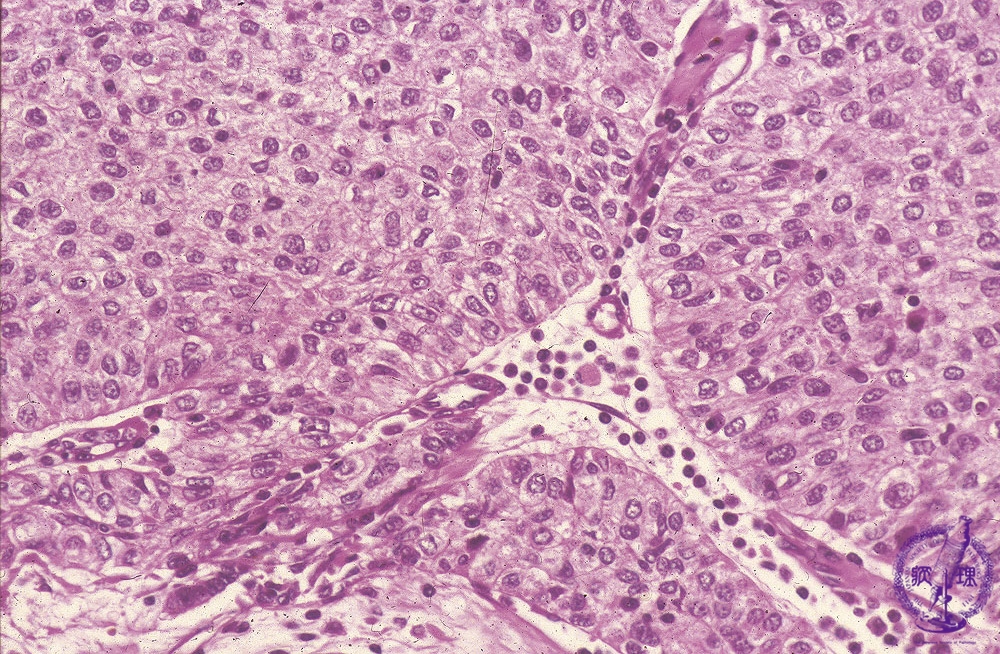

Microscopic view (high power view): Type B3 thymoma (epithelial thymoma) (WHO classification). Large, polygonal epithelial tumor cells grow in sheets without infiltrating lymphocytes. The perivascular spaces (★) seen centrally surrounding small capillaries (arrow) are a finding specific to thymoma.